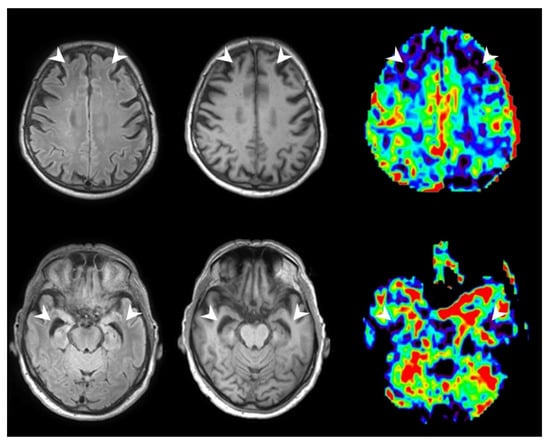

3.2.3. Patients with AD